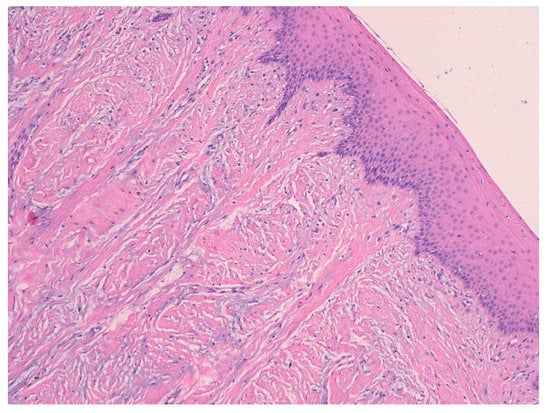

3.1. Histological Characteristics